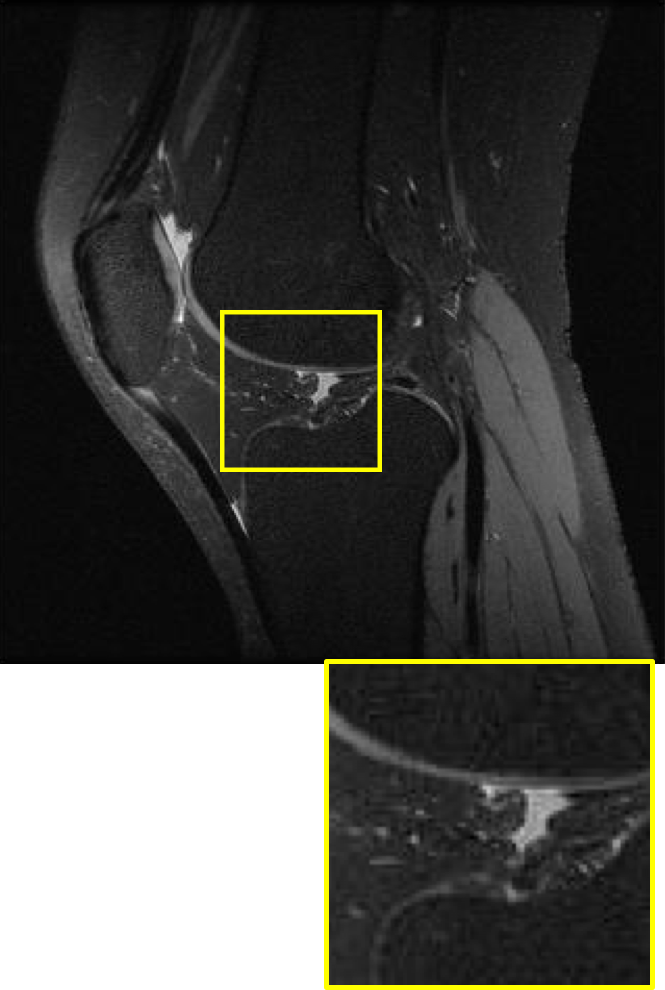

CS MR measurement matrix

LDAMP SURE was applied to CS-MRI reconstruction problem to demonstrate its generality and to show its performance on images that contain structures different from natural image dataset. We compared LDAMP SURE with state-of-the-art BM3D-AMP-MRI algorithm [16] for CS-MR image reconstruction along with TVAL3, BM3D-AMP, and dictionary learning method or DL-MRI [34]. Average image recovery PSNRs and run times are tabulated in Table 3. Figure 5 shows that our proposed method yielded state-of-the-art performance, close to the ground truth. The results reveal that proposed LDAMP SURE-T outperforms existing algorithms in all sampling ratios.

Ground truth

Ground truth

TVAL3

BM3D-AMP

DL-MRI

BM3D-AMP-MRI

LDAMP SURE-T